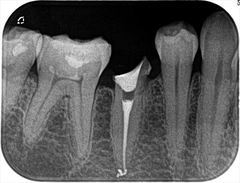

根管治療広島

右上第二小臼歯の再根管治療を終えました。2020.01.25